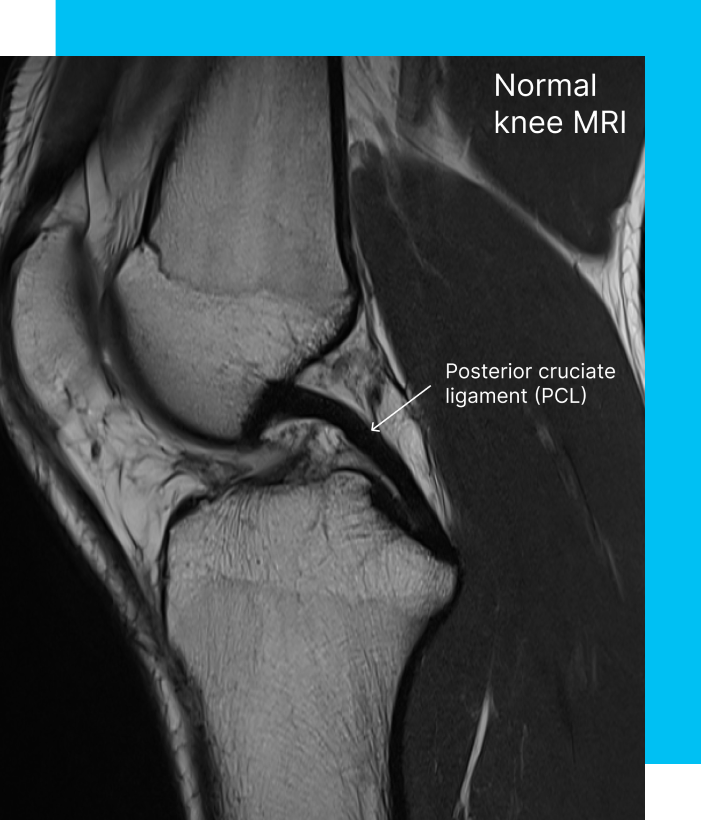

If PCL reconstruction is on your horizon, knowing the ins and outs of the operation is just the start. The PCL is a mainstay in knee stability, and when damaged, fixing it is key to resuming your usual life. PCL surgery aims to fix or rebuild the hurt ligament, restoring your knee to its pre-injury state.